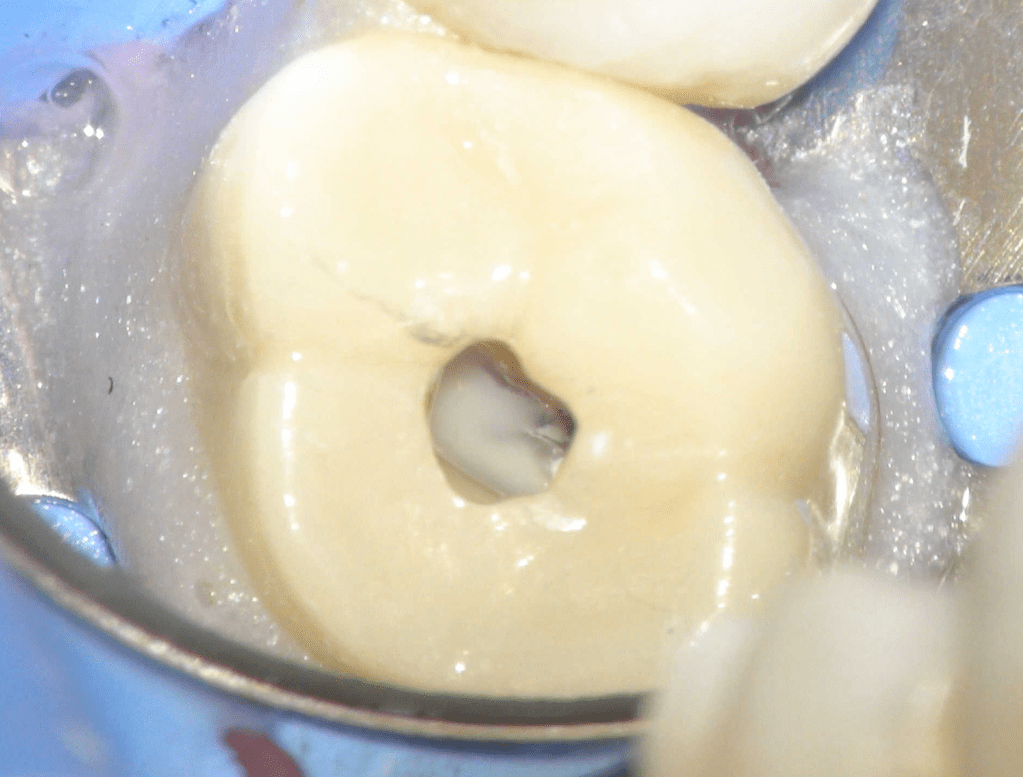

Reabsorción interna

Reco pared vesticular